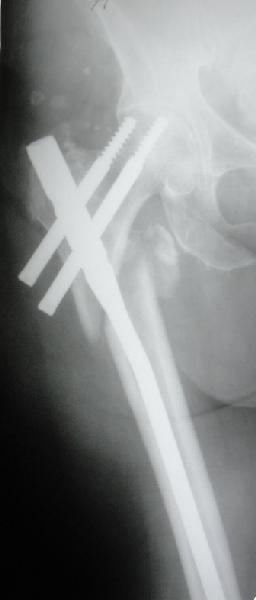

Диаметр гаммы в диафизарной части ~11 мм. А диаметр канала, тем более у пожилых с остеопорозом, может быть мм 15. Даже рассверливать обычно не приходится, после формирования широкого канала в вертельной области можно сразу толкать гвоздь, он влетает, как карандаш в стакан. Так что соответствия диаметров не бывает никогда. Однако представленная ситуация случается далеко не каждый раз. Если гвоздь в центральном отломке входит чуть медиальнее верхушки вертела, и идет вдоль передне-латеральной стенки центрального отломка, то все будет хорошо.

В приложении похожий пример, к счастью, пациентка появилась не после, а "за полчаса" до протрузии. Пересинтезировали с исправлением ошибок.